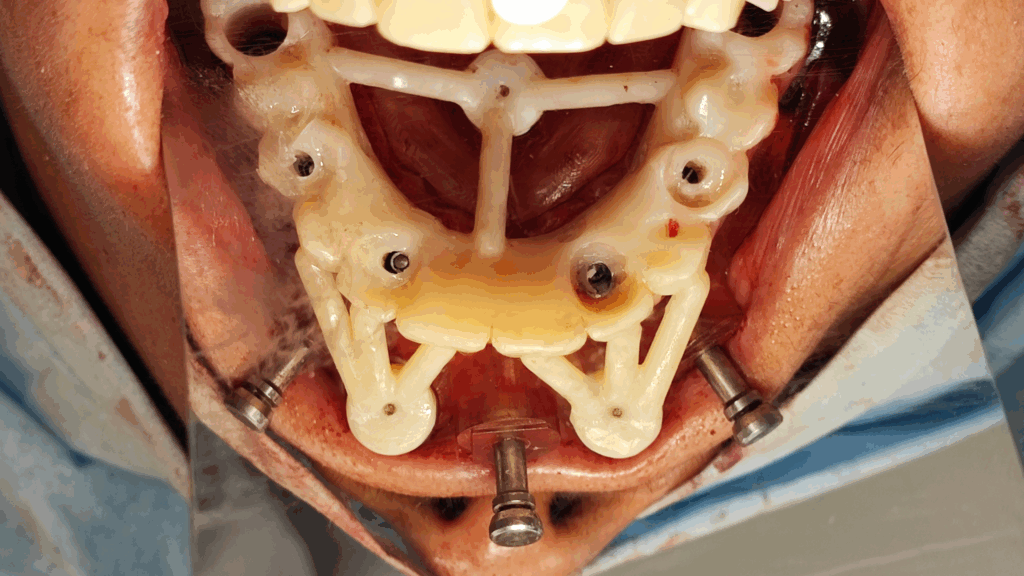

Rehabilitación completa maxilar (Full Arch)

Paciente: mujer, 59 años, edentulismo parcial.

Tratamiento: colocación de 6 implantes inmediatos con férulas apilables y prótesis provisional instantánea parcial.

Tiempo de intervención: 2 horas y 30 minutos.

Beneficios: intervención rápida y precisa, manejo conservador del tejido blando, estética y funcionalidad instantánea, alta satisfacción del paciente.

Estos casos ilustran cómo nuestro flujo BRDP y la cocreación clínica permiten resultados predecibles y eficientes, optimizando tanto el tiempo de sillón como la experiencia de paciente y clínica.